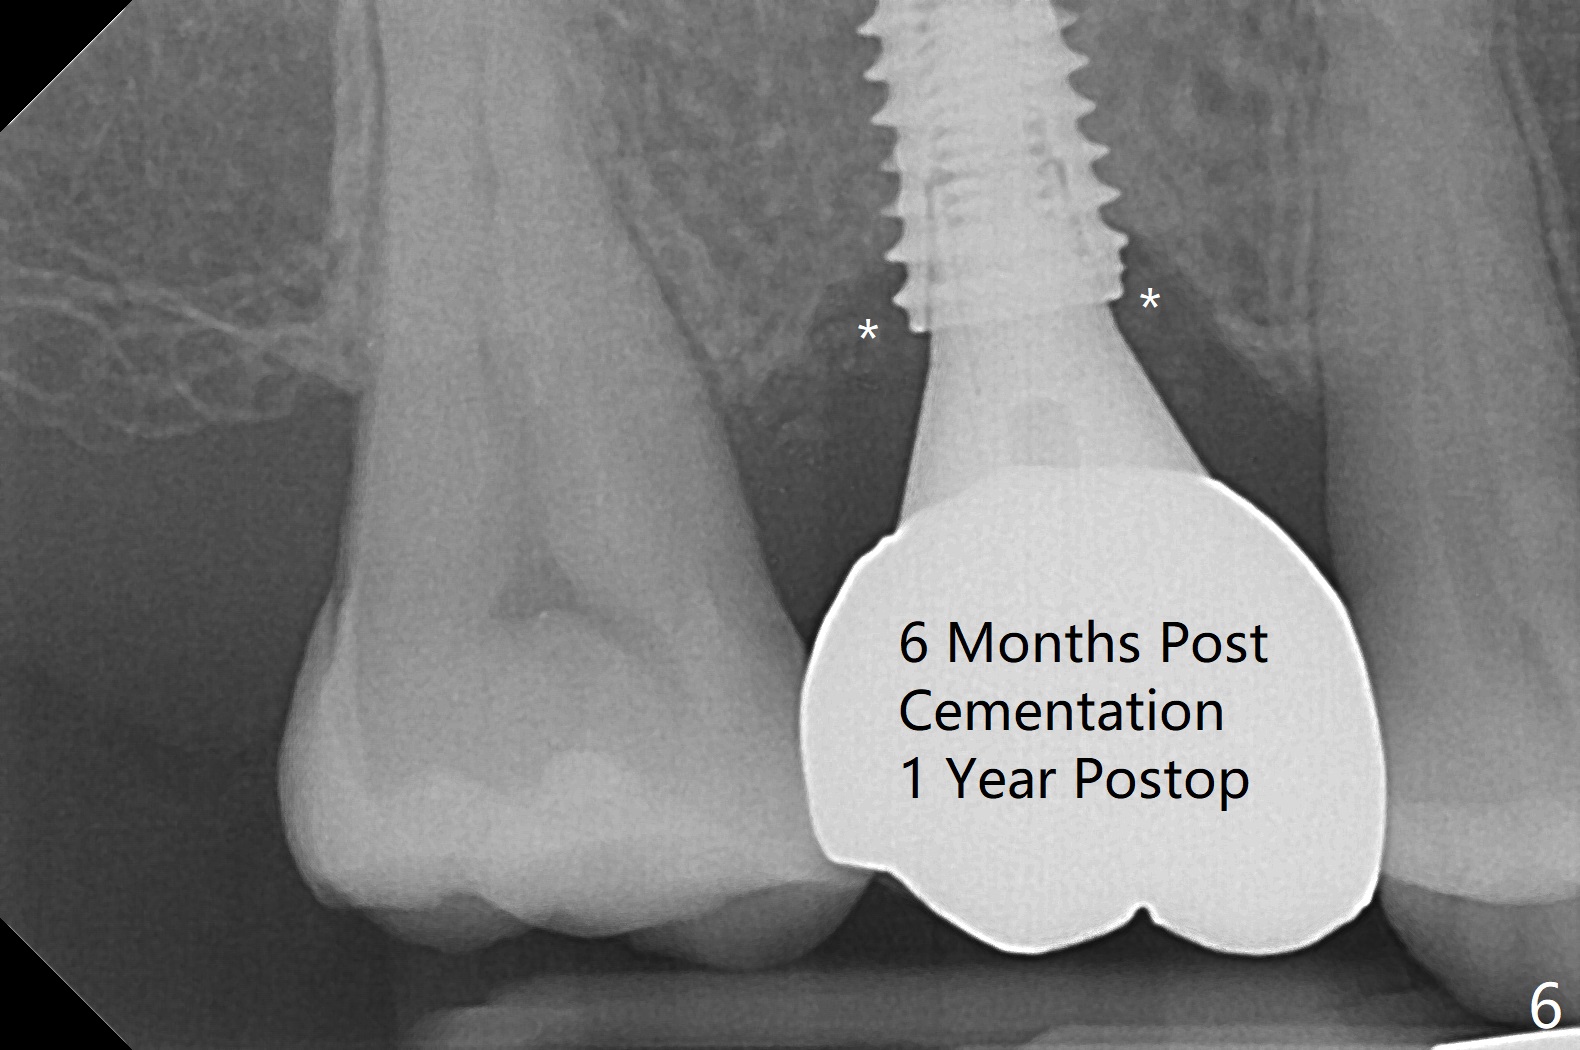

There is mild crestal bone loss 4.5 months postop (Fig.5).  When the patient returns for periodic exam and prophy 6 months post cementation, the crown is found to be loose, which is more likely associated with heavy mastication (long roots) and poor crown/implant ratio.  Since the distal contact is light, the case returns to lab.  PA taken following reseating the repaired abutment/crown shows crestal bone loss, which may be associated with the narrow ridge and/or the loose abutment.  The gingival cuff is less healthy (Fig.6).  The screw becomes loose again 4 months later.  When it is retightened, the distal proximal contact turns open (Fig.7 ^).  The crown appears to turn with the underlying abutment (Fig.8).  After breaking proximal contacts, the crown/abutment is retightened and pick up impression is taken.  It is likely that the abutment was not seated right when abutment-level impression was taken.  The crown table is slightly oversized (Fig.8). Three months later, the screw becomes loose for the 3rd time (unilateral mastication, pain at #19 without RCT).  The abutment hex is not worn.  The crown is removed and the abutment is reseated and torqued 30 Ncm.  Impression is taken for new crown.  The latter is cemented without removing the abutment (Fig.9 (note bone loss)).  In fact the crown/abutment should have been torqued with screw driver buried in place!